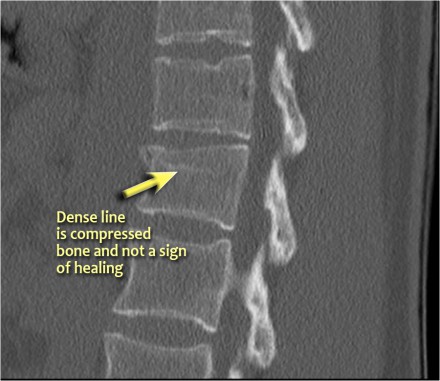

Notice the horizontal band of density, which is often described as sclerosis.

This density does not mean that it involves an older fracture that is already healing with sclerosis.

This is merely a sign of trabecular impaction in an acute fracture.